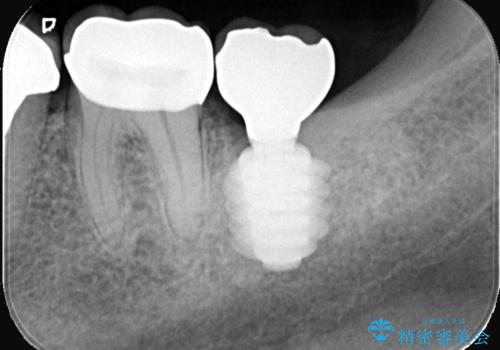

- 過去にヘミセクションが行われていたと思われる左下7番は、大きな歯根嚢胞および根尖病変が認められ、さらに骨縁下カリエスを伴っており、歯肉には瘻孔が形成されている状態でした。

保存は困難と判断し、左下7番は抜歯即時インプラントによる治療を行いました。